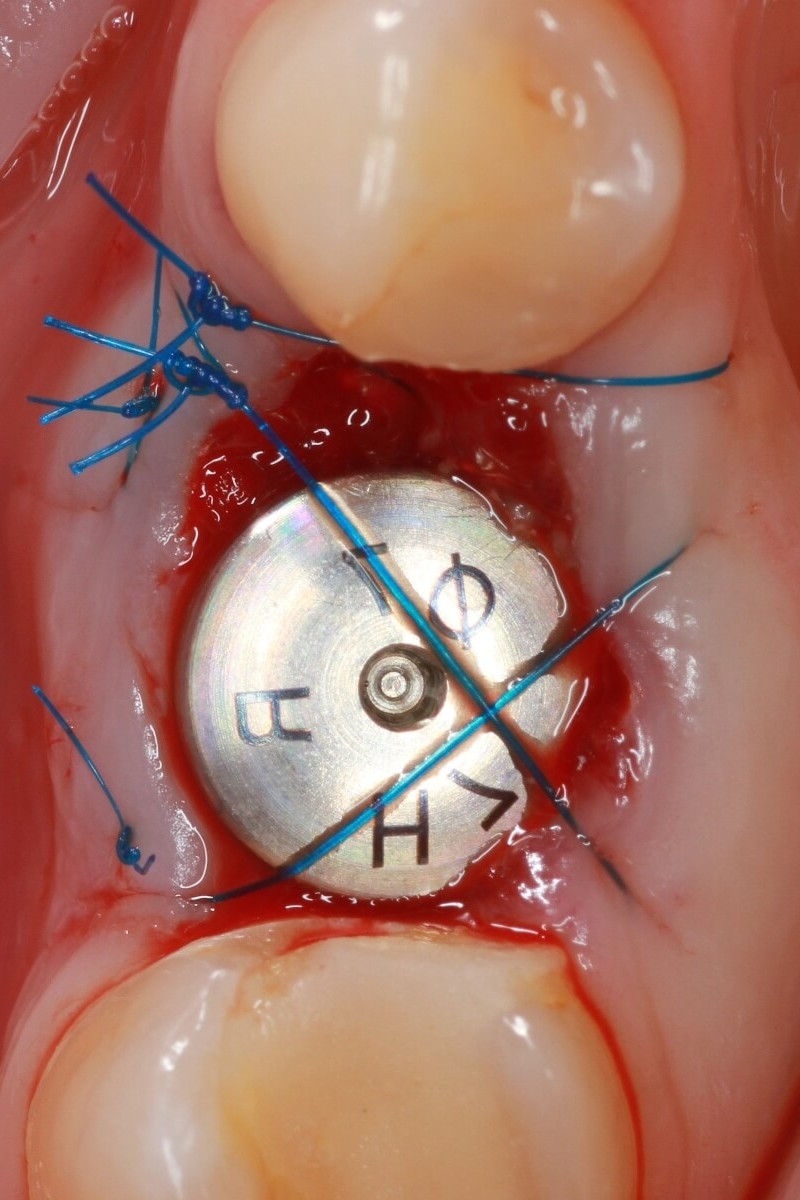

Installing the healing abutment

We install the gingiva former for 2-3 weeks in order to obtain an aesthetic gingival margin for subsequent prosthetics.